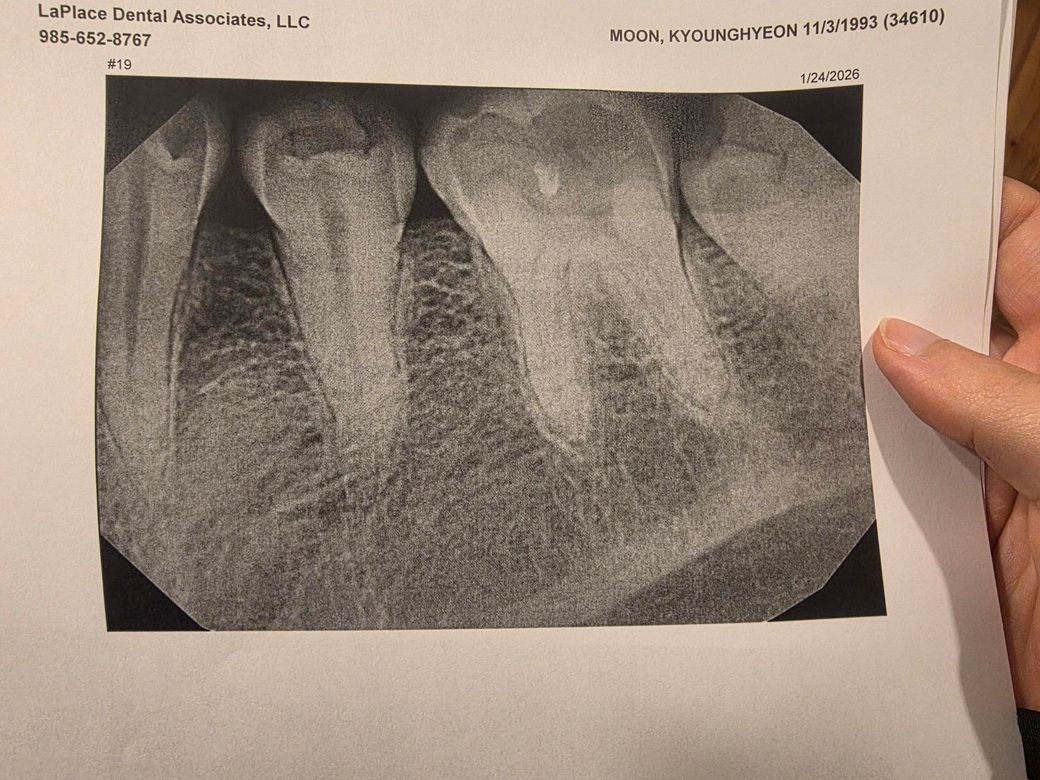

어금니에 2/3가 금이 간 상황인데 어때보이냐니까 자꾸 다른병원갔다가 오래요 느낌에 과잉진료같은데 이거 이정도면 치아를 어떻게 해야하는게 맞나요? 사진상 보철물 반대편인 우측 세컨드 몰러입니다

• 2번 째 사진

2. 어금니 2/3 금이간 상태면 일반적으로 신경치료하고 크라운 씌웁니다